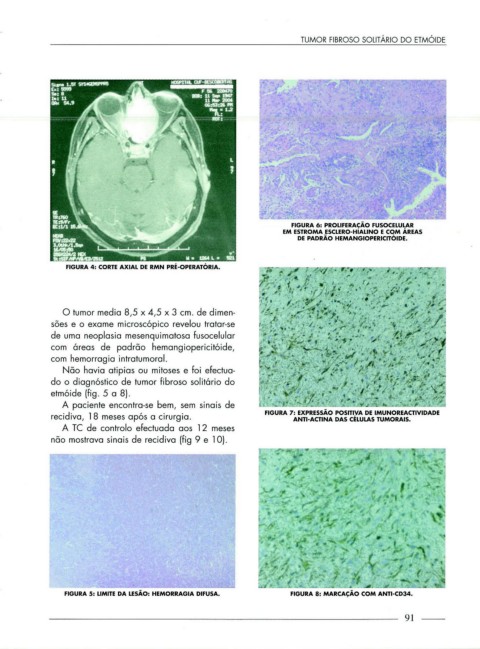

FIGURA 6: PROLIFERAÇÃO FUSOCELULAR

EM ESTROMA ESCLERO-HIALINO E COM ÁREAS

DE PADRÃO HEMANGIOPERICITÓIDE.

O tumor media 8,5 x 4,5 x 3 cm. de dimen-

sões e o exame microscópico revelou tratar-se

de uma neoplasia mesenquimatosa fusocelular

com áreas de padrão hemangiopericitóide,

com hemorragia intratumoral.

Não havia atipias ou mitoses e foi efectua-

do o diagnóstico de tumor fibroso solitário do

etmóide (fig. 5 a 8).

FIGURA 7: EXPRESSÃO POSITIVA DE IMUNOREACTIVIDADE

recidiva, 18 meses após a cirurgia. ANTI-ACTINA DAS CÉLULAS TUMORAIS.

A TC de controlo efectuada aos 12 meses

não mostrava sinais de recidiva (fig 9 e 1 0 ).

FIGURA 5: LIMITE DA LESÃO: HEMORRAGIA DIFUSA. FIGURA 8: MARCAÇÃO COM ANTI-CD34.